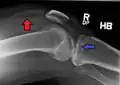

-

Lipohemarthrosis (presence of fat and blood from bone marrow in the joint space after an intraarticular fracture) seen on X-ray in a person with a subtle tibial plateau fracture -

Lipohemarthrosis due to a tibial plateau fracture -